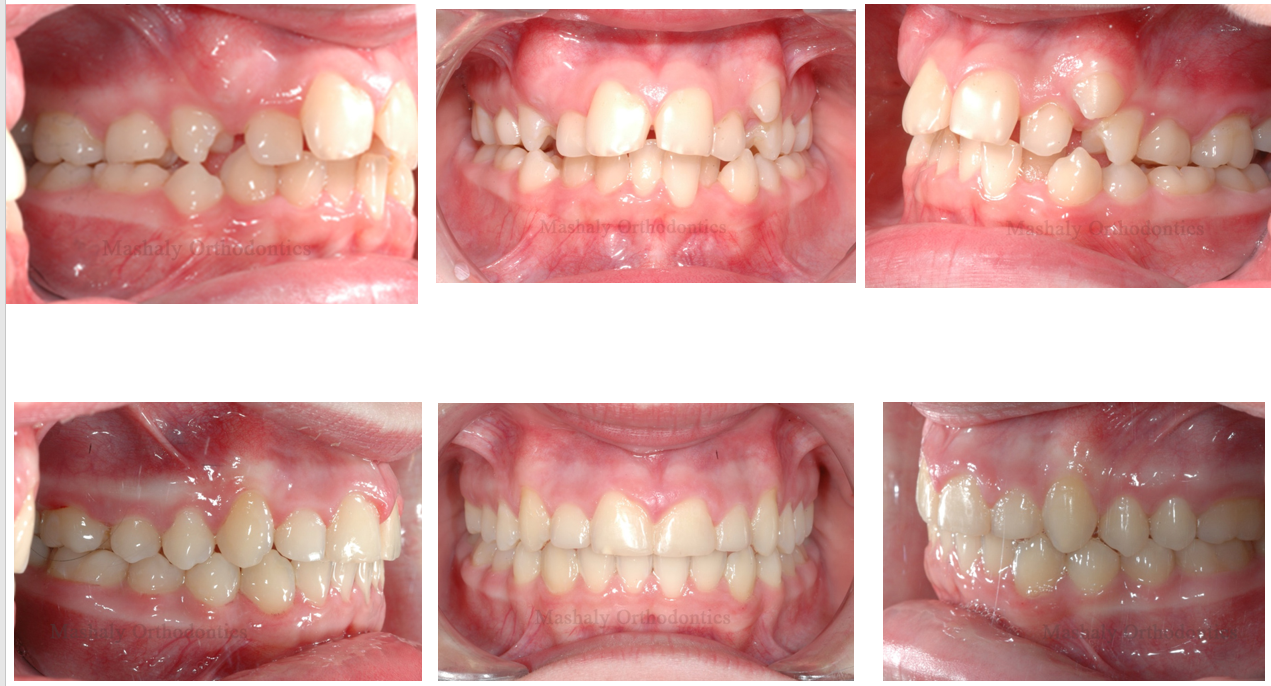

Orthodontics is a dental specialty that helps treat misalignment of teeth, malocclusion

(improper bite), and other related issues. Orthodontic treatment goes beyond addressing cosmetic concerns and is also used to treat various medical conditions such as impacted teeth and other dental problems.